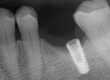

The end photographs are of a new Astra Tx aqua implant as an undamaged control. The center four images are of the postop impression, again turned 90 degrees to evaluate each side.

While significant threads have been cleared, there was some additional internal thread damage due to the difficulty in achieving and keeping the boring operation concentric. This can be viewed on the same side in the threads, apical to the prior significant eccentric drilling. This was caused by deflection of the enlarging drills, terminating with a 1.25mm predrill, when they were introduced to eliminate the screw core. This step is mandatory prior to introducing a tap, as a tap cannot negotiate an obstruction, other than eliminating the small male thread fragments. There is no room for concentric error at that diameter. The amount of thread blunting can be visualized in views 1 and 3, with the right and left arrows. This blunting appears as a filled in area by the impression material.